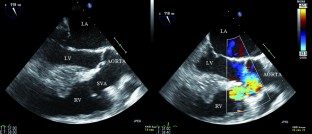

Figure 2